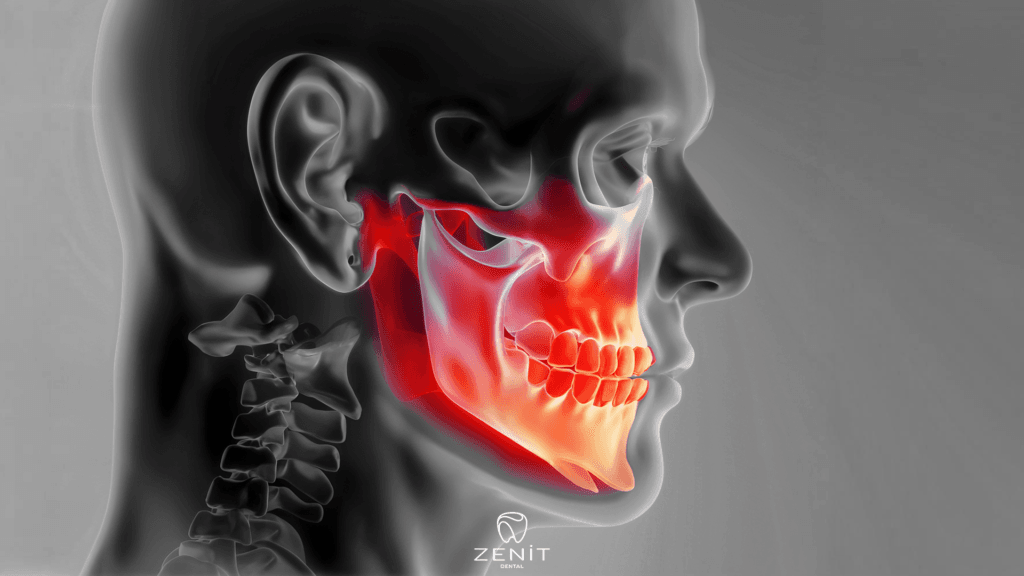

As with every surgical procedure, zygoma implants have some risks and side effects. However, these risks are minimized when performed by an experienced surgeon. Possible risks are:

- Sinus Problems: Since zygomatic implants are placed in areas close to the sinus cavities, sinus problems may occur. However, with the right techniques, this risk is minimized.

- Pain and Swelling: It is normal to experience pain and swelling after surgery. These symptoms usually subside within a few days and can be controlled with painkillers.